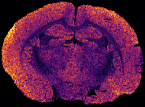

In MS imaging, data is collected from different positions in the sample, resulting in mass spectra as shown above. When the imaging analysis is complete, a single mass peak and its m/z value can be selected from the spectral data, representing a single compound detected in the sample. By plotting the intensity of this mass peak from each analysed position, MS images (heat maps) can be generated to show its relative change and thus how the compound is distributed in the sample area. For example, negative ion IR-LAAPPI MS images of a 20 μm thick slice of whole rat brain tissue measured at 70 μm spatial resolution, consisting of approximately 30,000 pixels, are shown below to illustrate how different lipid species are distributed in the brain.

| Photo | MS image | MS image | MS image |

|---|---|---|---|

![]() |

| Myelin-stained brain | GalCer(38:1) | PE(34:0) | PE-P(36:4) |

Conventional imaging techniques such as positron emission tomography, autoradiography, and immunohistochemistry, can only image a few radiotracers, radioisotopes, or antibody-labeled molecules at a time, respectively, as presented with the myelin-stained photo above. MS imaging techniques like IR-LAAPPI and IR-LAESI can image hundreds of compounds simultaneously, thereby providing a valuable tool for finding differences between sample types such as malignant and benign tumors.